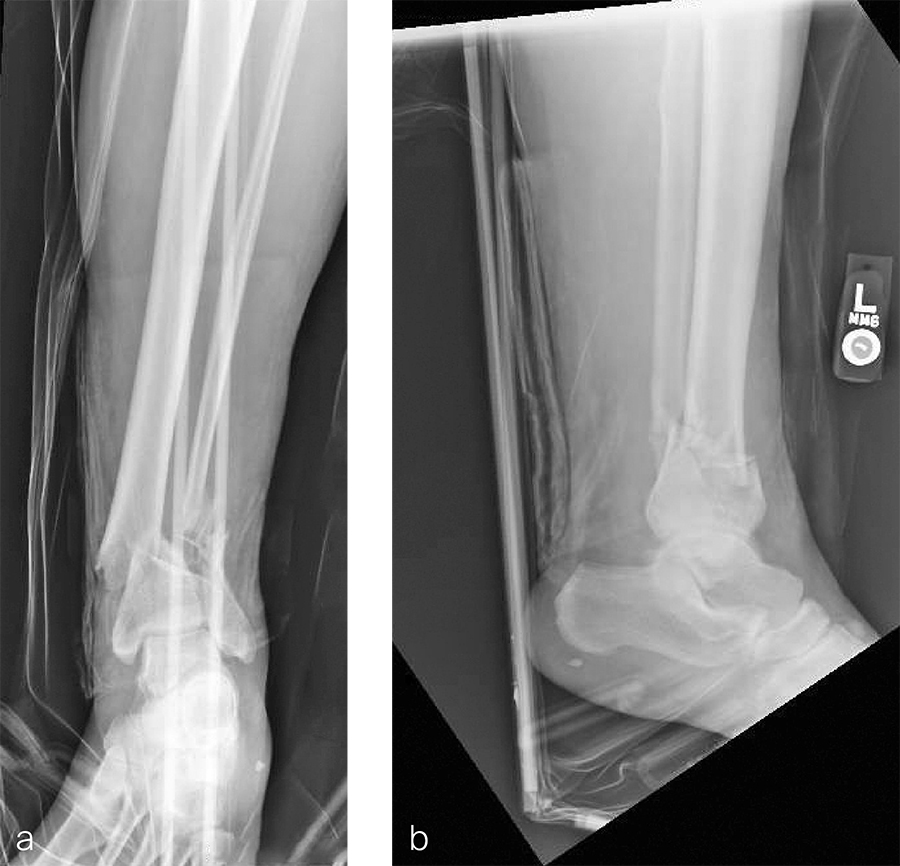

After repeated incision and drainage, 2 days later the fracture was repaired with an anterior lateral tibial plafond plate (Fig 2). Vancomycin and tobramycin impregnated antibiotic beads were placed in the bone defect.

The patient was discharged on hospital day 6 to a rehabilitation facility with his left lower extremity in a splint and touch down weight bear allowance. He returned 2 weeks later with drainage from the medial traumatic wound. In addition, he had a gastrointestinal bleed from use of nonsteroidal antiinflammatory drugs. Once the gastrointestinal bleed was stabilized, he was taken the next day to the OR for another incision and drainage. Further, more significant, devitalized bone was resected, and an antibiotic cement spacer was placed (Fig 3). Deep culture samples were taken despite knowing the antibiotic resorbable beads had been placed in the wound at the time of initial closure. The plate was left in place, but a planned exchange plate/nailing was to be performed pending final culture results.

Cultures eventually yielded Klebsiella pneumoniae and Enterobacter cloacae. The patient was administered intravenous antibiotics for 6 weeks and was discharged home with therapy and nursing. He returned to the clinic with wound breakdown and an exposed cement spacer at 10 weeks after injury. Further bone debridement, spacer exchange, repeated culture samples, and plastic surgery were undertaken to help with wound coverage with a rotational flap. The microbiological culture was still positive for Klebsiella pneumoniae.

Two months later, the patient had a staged cement spacer removal and hardware removal followed by a new spacer placement (Fig 4). When microbiological cultures were negative for 5 days he was taken to the OR for definitive fixation and bone grafting. RIA bone graft from the ipsilateral femur was taken, a new anterior lateral plate was placed with an adjunct IM nail (and angle stable screws) as the distal plafond was now one articular block (Fig 5).